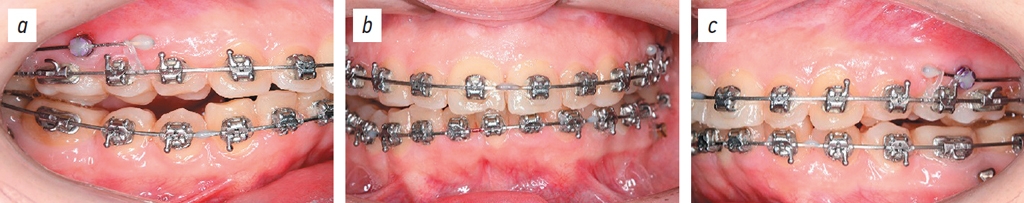

Empower braces (CuNiTi 0.14; American Orthodontics, USA) were installed on the maxilla (Figs. 10, 11).

Fig. 10. Dental arches after braces placement, lateral right projection (a), posteroanterior projection (b), left side projection (c).

Рис. 10. Зубные ряды после устновления брекет-системы: боковая правая проекция (a), передняя проекция (b), боковая левая проекция (c).

One month after braces were installed on the maxilla, nano-osteoperforation of the roots of teeth 7, 6, 9, 10, and 11 (ISO designations 12, 13, 21, 22, and 23, respectively) was performed, and a BioEdge 16×16 archwire was installed (Fig. 12).

Fig. 12. Dental arches after nano-osteoperforations: right lateral projection (a), posteroanterior projection (b), left lateral projection (c).

Рис. 12. Зубные ряды после нано-остеоперфораций: боковая правая проекция (a), прямая проекция (b), боковая левая проекция (c).